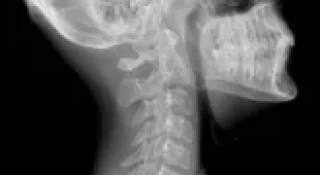

Рентген шейного отдела

Как проводится рентген шейного отдела

Никакой подготовки для этого со стороны пациента не требуется. Процедура занимает буквально пятнадцать минут общего времени. Доктор делает снимки в двух проекциях: спереди, когда шею фотографируют, прислонив ее передней частью к аппарату, а также когда снимок получают через открытый рот и сбоку. Важно, чтобы пациент при этом не двигался, иначе рассмотреть полученные результаты будет сложно, они будут искаженными и не дадут возможности провести правильную диагностику.